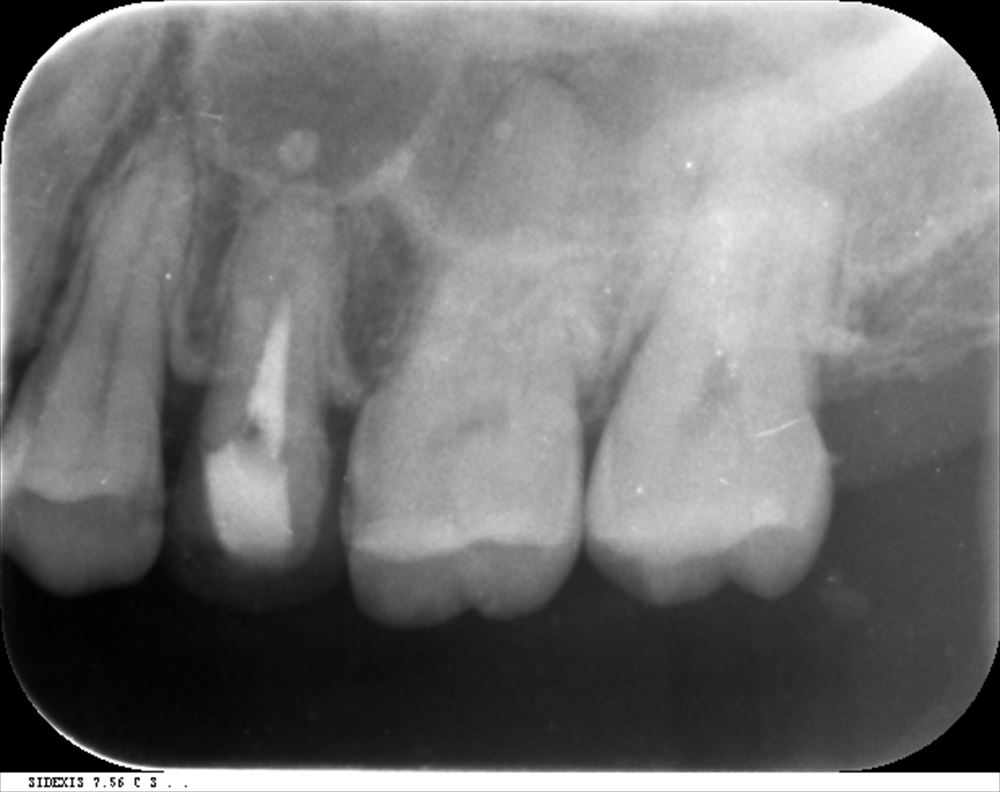

術前はこんな。上顎洞まで腫れていました。

本日。良かったです!!嬉しい!!